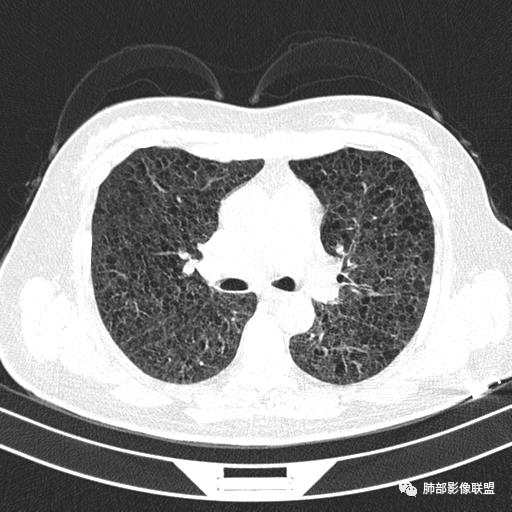

双肺弥漫囊腔,累及肋膈角,囊腔形态相对规则单一。

CT平扫示双肺弥漫分布大小不等囊状薄壁透光区,无内、中、外带分布差异,间质稍示增厚。拟LAM

中年女性育龄期妇女,咳嗽气喘,无吸烟史,有苯吸入史。影像:双肺弥漫均匀小囊腔,无明显分布优势,囊腔形态欠规则,壁薄,部分囊腔边缘血管征,伴双肺弥漫磨玻璃影,无结节,考虑lam,鉴别苯中毒肺损伤,囊腔多有分布优势,小叶中心分布为主,形态规整等

女,46,活动性气喘1年。苯吸入史半年。胸部CT:两肺弥漫囊腔,上至肺尖,下至肋膈角,形态类似小囊腔。考虑:LAM,鉴别LIP,BHD,PLCH等。

CT表现:双肺弥漫大小不等的薄壁囊腔,囊壁<2mm,外形规则,血管影多位于囊腔周围,囊腔之间肺组织正常,随着疾病进展到晚期,囊腔变大、增多,不可胜数,囊腔可融合成较大的囊,与肺气肿相似,形成间质性肺纤维化。部分病例可出现结节影。